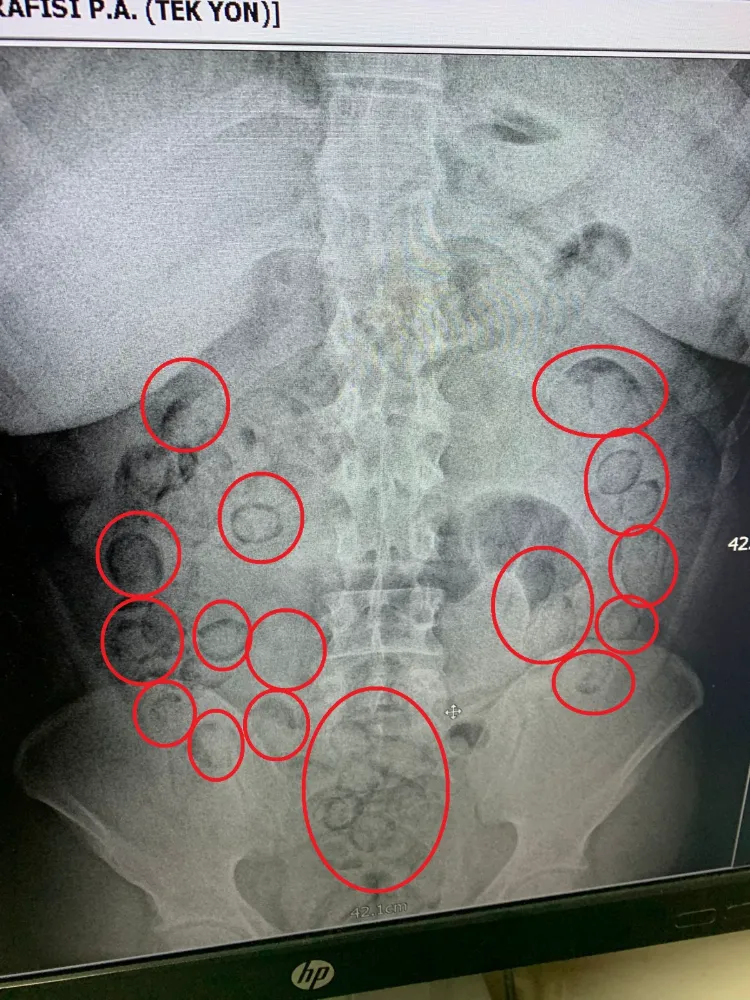

Aksaray Eğitim ve Araştırma Hastanesi’nde yapılan iç beden muayenesinde, zanlının midesinde toplam 101 parça halinde 433 gram metamfetamin gizlediği ortaya çıktı.